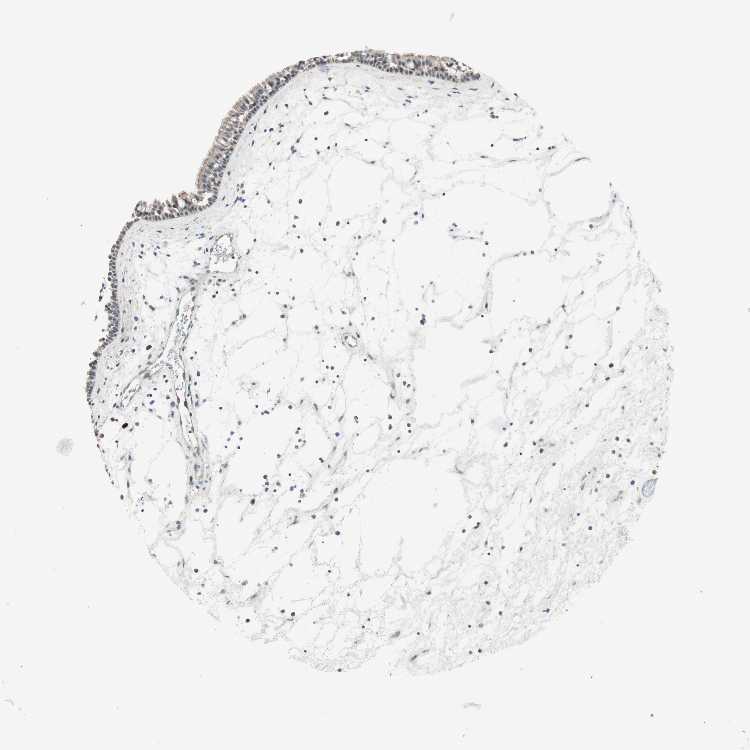

TISSUE PRIMARY DATA NASOPHARYNX Show tissue menu

NASOPHARYNX - Antibody stainingi

Antibody staining in the annotated cell types in the current human tissue is reported as not detected, low, medium, or high, based on conventional immunohistochemistry profiling in selected tissues. This score is based on the combination of the staining intensity and fraction of stained cells.

Each image is clickable and will lead to virtual microscopy that enables deeper exploration of all samples and also displays staining intensity scores, fraction scores and subcellular localization as well as patient and tissue information for each sample.

Antibody HPA007172Antibody CAB026471

Respiratory epithelial cells Not detectedHigh